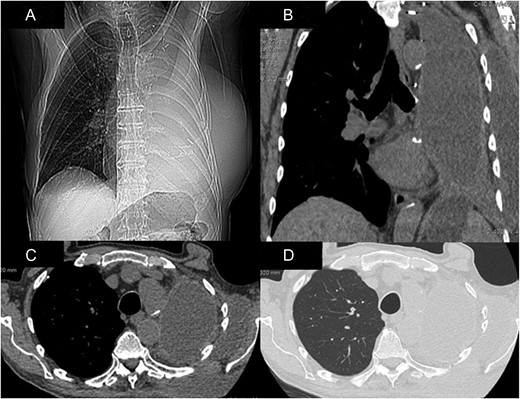

An 83-year-old man, who had undergone a left pneumonectomy for primary lung cancer 33 months earlier, presented in our clinic complaining of several weeks history of significant weight loss, dyspnea and a progressively increasing and painful swelling of his left chest. Physical examination revealed an impressively large, soft and balottable mass located at the level of the previous left thoracotomy (Fig. 1). Chest computed tomography (CT)-scan showed extensive herniation of the post-pneumonectomy cavity through the rib spaces, contained by the pleura (Fig. 2A–D). The patient denied recent history of chest trauma or episodes of violent cough, and all laboratory tests, including inflammatory markers, were unremarkable. Given the size of the herniation and the patient’s progressively worsening symptoms, surgical treatment for this unusual condition was deemed necessary. Surgery was carried out via a standard postero-lateral thoracotomy at the level of the old incision. The massive pleural hernia sac was immediately evident (Fig. 3A) and, once opened, ~1700 ml pleural fluid of gelatinous consistence was aspirated. The herniation site was identified in the previously opened intercostal space, in an antero-lateral position (Fig. 3B). The large sac (21 × 18 cm2) was excised and removed (Fig. 3C), while the defect was repaired with a polypropylene mesh, fixed by interrupted sutures and covered with the edge of the adjacent serratus anterior muscle (Fig. 3D). Histology results of the pleural hernia specimen showed inflammatory changes and granulation tissue. Postoperative recovery was uneventful and patient was discharged with minimal pain after 72 h, with an elasticated vest to be worn for 6 weeks. At 6-month follow-up, patient is well and there is no evidence of recurrence.

CT-scan demonstrating the impressive hernia in coronal views (A and B) and axial views (C and D).